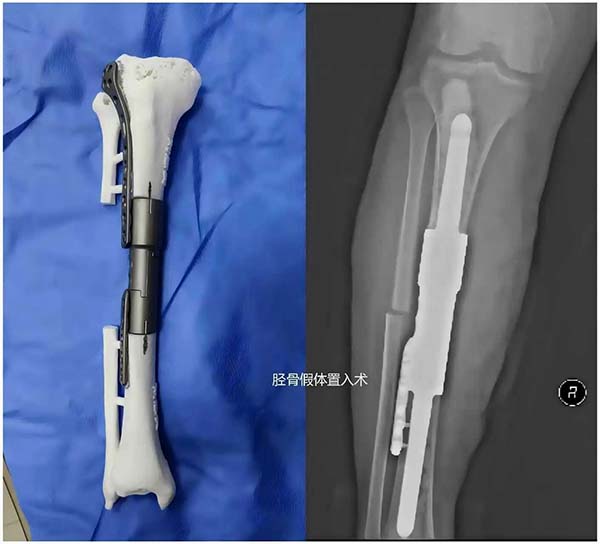

3D打印实现“精准保肢”:在骨肿瘤保肢治疗中成功应用3D打印定制假体技术,根据患者解剖结构“量身定制”假体,实现从“将就”到“讲究”的跨越,最大程度保留肢体功能,让患者不仅“活得长”,更能“活得好”。